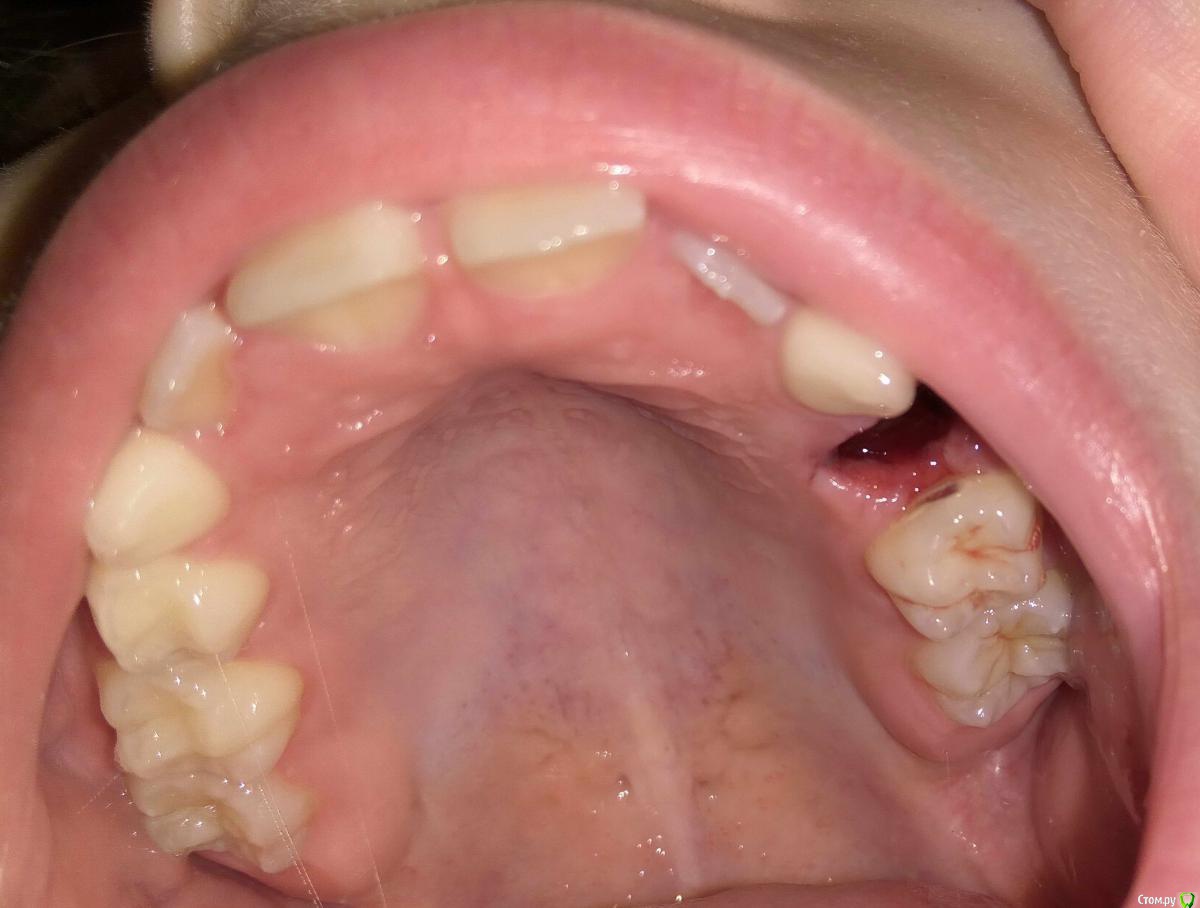

ANTL Опубликовано 11 июня, 2016 Автор Поделиться Опубликовано 11 июня, 2016 Сколько лет ребенку? Покажите фото во рту Ребенку семь с половиной лет. Приложил фото ранки во рту. Ссылка на комментарий

red_butler Опубликовано 11 июня, 2016 Поделиться Опубликовано 11 июня, 2016 Зуб то молочный, но зачем удалили не понял. Rg делали? Ссылка на комментарий

Brigita Опубликовано 11 июня, 2016 Поделиться Опубликовано 11 июня, 2016 ну теперь то уж не вернешь.До постоянного далеко еще, как минимум два года Ссылка на комментарий

Yana guapa Опубликовано 26 июня, 2016 Поделиться Опубликовано 26 июня, 2016 Ребенку семь с половиной лет. Приложил фото ранки во рту. 5.jpg6.jpgна молочной пятерке кариес (со стороны отсутствующего зуба), можно и нужно полечить , пока в пульпит не превратился и пока вам опять не удалили хороший зуб)) Ссылка на комментарий